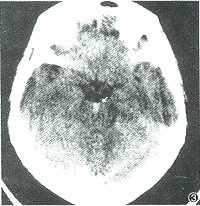

顱內脊索瘤X線表現頭顱脊索瘤多見於顱底、蝶鞍附近,蝶枕軟骨連合處及岩骨等處。骨質破壞邊界尚清楚,可有碎骨小片殘留和斑片狀鈣化物質沉積。並可有軟組織腫塊凸入鼻咽腔,一般較大,邊緣光滑。脊索瘤腫塊突出顱腔時可使鈣化松果體移位,偶可引起顱內高壓。頸椎的脊索瘤常位於上頸椎,尤在頸椎和枕骨交界處,多累及椎體、椎弓根偶爾也可受到侵犯,軟組織腫塊,常為突出的早期表現。胸椎脊索瘤較少見。